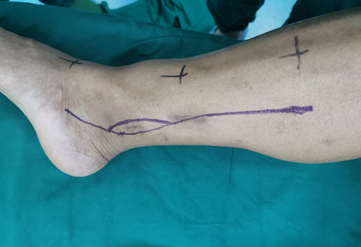

手术切口设计

为同时解决胫骨远端骨肉瘤病灶切除及一期完成下肢保肢及踝关节功能重建这两个问题,林荔军主任独具匠心的提出采用瘤段切除+3D打印胫骨远端假体进行功能重建的处理方案。根据肿瘤侵犯范围设计切除范围置入根据患者CT数据的个体化3D打印胫骨远端假体,采用关节接触面的骨长入设计及关节远端螺钉钉道术前预计,为假体远端的骨长入提供近期及远期的稳定性。该方案国内外均无相关报道,为此林荔军主任与华钛三维吴鑫华院士团队成立了联合攻关组,历经10余次修改、有限元分析、假体打印、虚拟手术及力学测试等,最终确定手术方案及所需的关节假体。